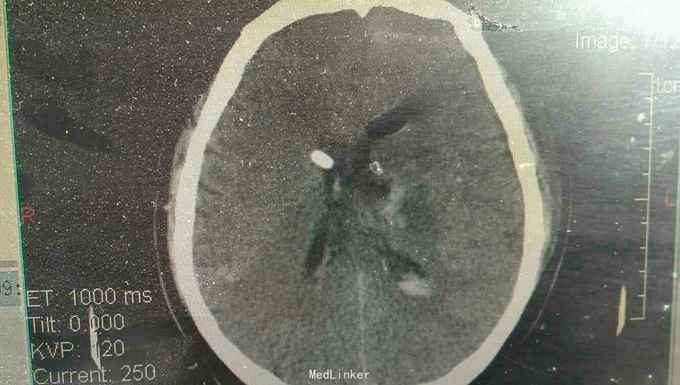

患者男性,56岁。以突发头痛伴意识不清半小时入院。患者入院半小时前突然自觉头痛,性质剧烈,呕吐多次,随即意识不清。来我院就诊。

浅昏迷状态,无语言。刺激后右侧肢体不动,左侧肢体可动。双侧瞳孔等大正圆,直径3.0毫米,光反射迟钝。右侧病理反射阳性。

脑出血,高血压病 急诊行微创硬通道内镜下血肿清除术,术中清除大部分血肿,患者术后第二天清醒右侧肢体三级,语言迟缓。